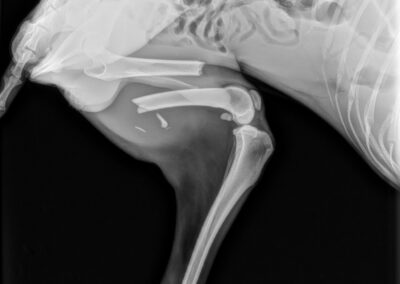

Marcus n’était plus qu’un véritable squelette, avec une fracture complexe du fémur au postérieur gauche. Il a dû vivre un véritable enfer, seul, blessé et affamé…

Il a été opéré en urgence à la clinique du refuge de la FBM, où il est actuellement en convalescence 🩺. La clinique est aujourd’hui totalement saturée, faisant face chaque jour à l’arrivée de nouveaux cas lourds : fractures, blessures graves, chiens brisés par la maltraitance et l’abandon… 😞 Malgré cette situation extrêmement difficile, Marcus a pu être pris en charge et bénéficie désormais de tous les soins nécessaires.